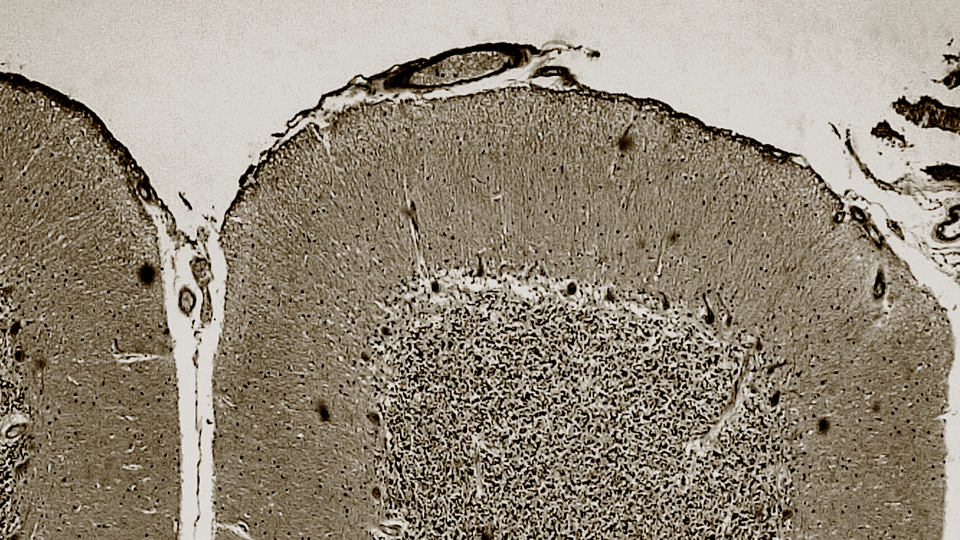

At first glance, the cerebellum looks a bit like a wrinkly, overgrown walnut shell. A closer look reveals two hemispheres with surface creases that sink down into deep grooves and split off into a network of coral-like branches. Peering through a microscope reveals a uniform pattern of densely packed cells. The cerebellum makes up only about 10 percent of the human brain’s mass but contains more than half of its neurons. Stretched out, the cerebellum’s surface area would be nearly 80 percent that of the cerebral cortex.

The highly organized, grid-like architecture of cells in the cerebellum has inspired some scientists to suggest that it carries out a single computation. Schmahmann has dubbed this hypothesis the “universal cerebellar transform.” Exactly which core computation could account for the cerebellum’s involvement in movement, cognition, and emotion remains an open question. But scientists have proposed a variety of possibilities, such as making and updating predictions or the precise timing of tasks.